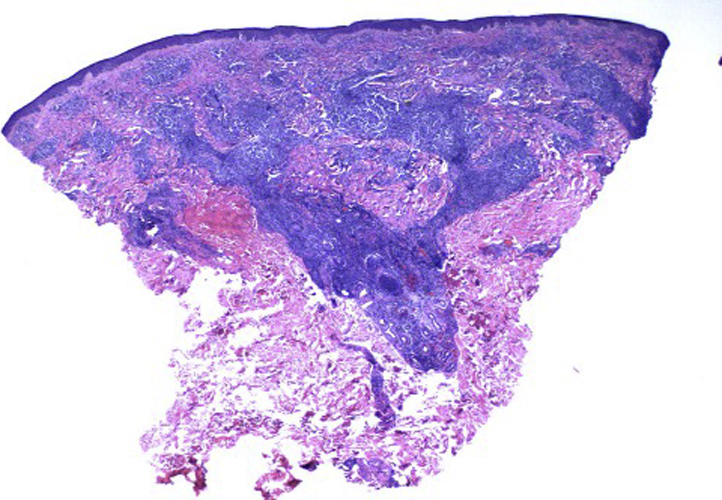

Fig 2.

A hematoxylin-eosin–stained punch biopsy collected at initial presentation. Dense superficial and deep perivascular and periadnexal dermal infiltrates comprising mostly small lymphocytes, some medium-sized lymphocytes, and a few plasma cells and histiocytes.